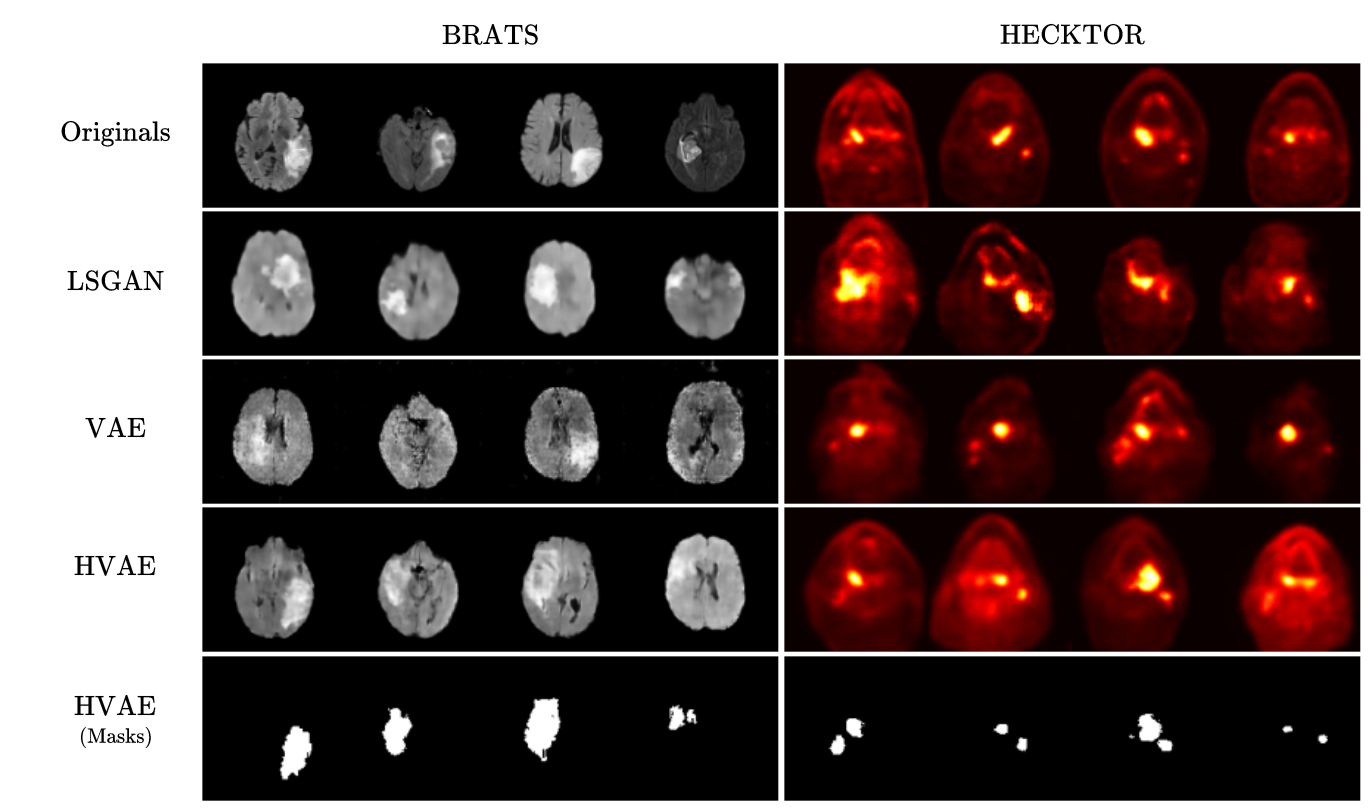

As depicted in Figure 2, we observe an enhancement in quality when transitioning from the VAE to the HVAE, resulting in a more realistic representation of tumor regions in MRI scans. Furthermore, the GAN architecture is particularly affected due to its high data requirements. These observations validate the hypothesis regarding the potential of VAEs and autoencoding architectures in dealing with insufficient datasets. Finally, we can note a decline in the DSC score beyond the inclusion of 500 synthetic images for the BRATS dataset, as indicated in Table 1. This decrease can be attributed to the imbalance between the number of real and synthetic images, introducing a bias that causes the model to primarily optimize the loss through synthetic images alone, negatively impacting the DSC score on the test set. However, it is worth mentioning that the DSC score starts decreasing beyond 200 synthetic MRIs for the LSGAN and vanilla VAE models, while this decrease occurs at more than 300 synthetic images for our archticture. This further demonstrates that the images generated by the HVAE are more realistic, and the U-Net architecture requires additional effort to perceive the perceptual difference between synthetic and real images.